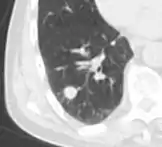

Lung nodule abutting a pulmonary cyst.[9]

• A lung nodule abutting a pulmonary cyst is a rare finding, yet indicating cancer.[9]